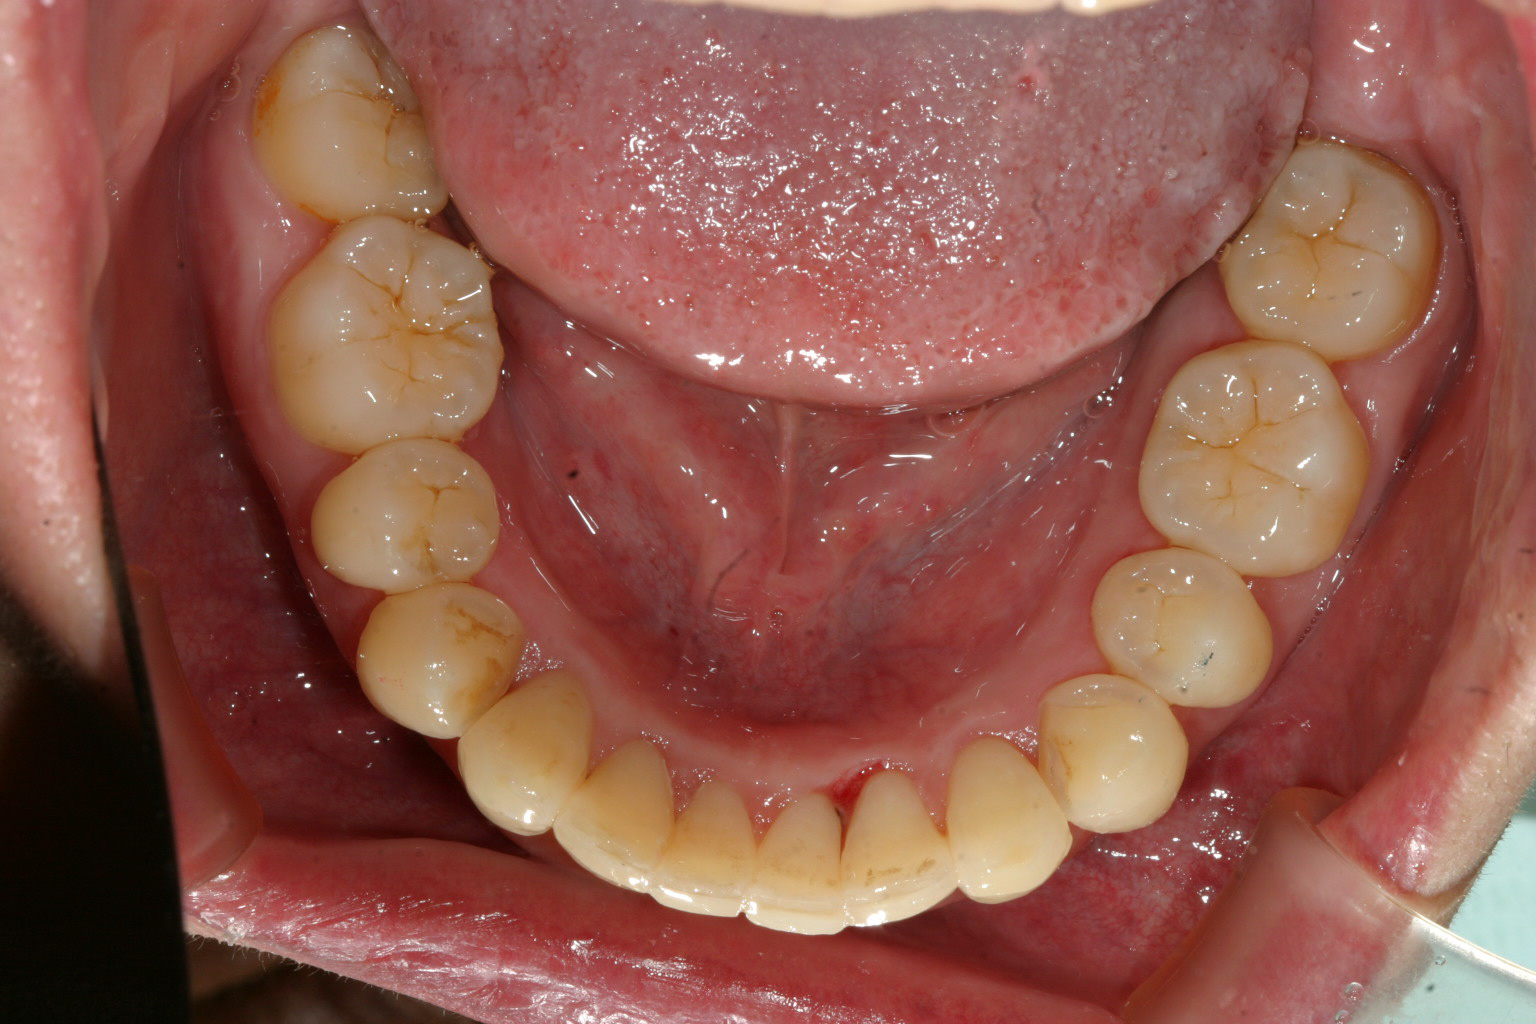

下顎の歯もガタガタになってます。

下顎のガタガタも綺麗に改善してます。